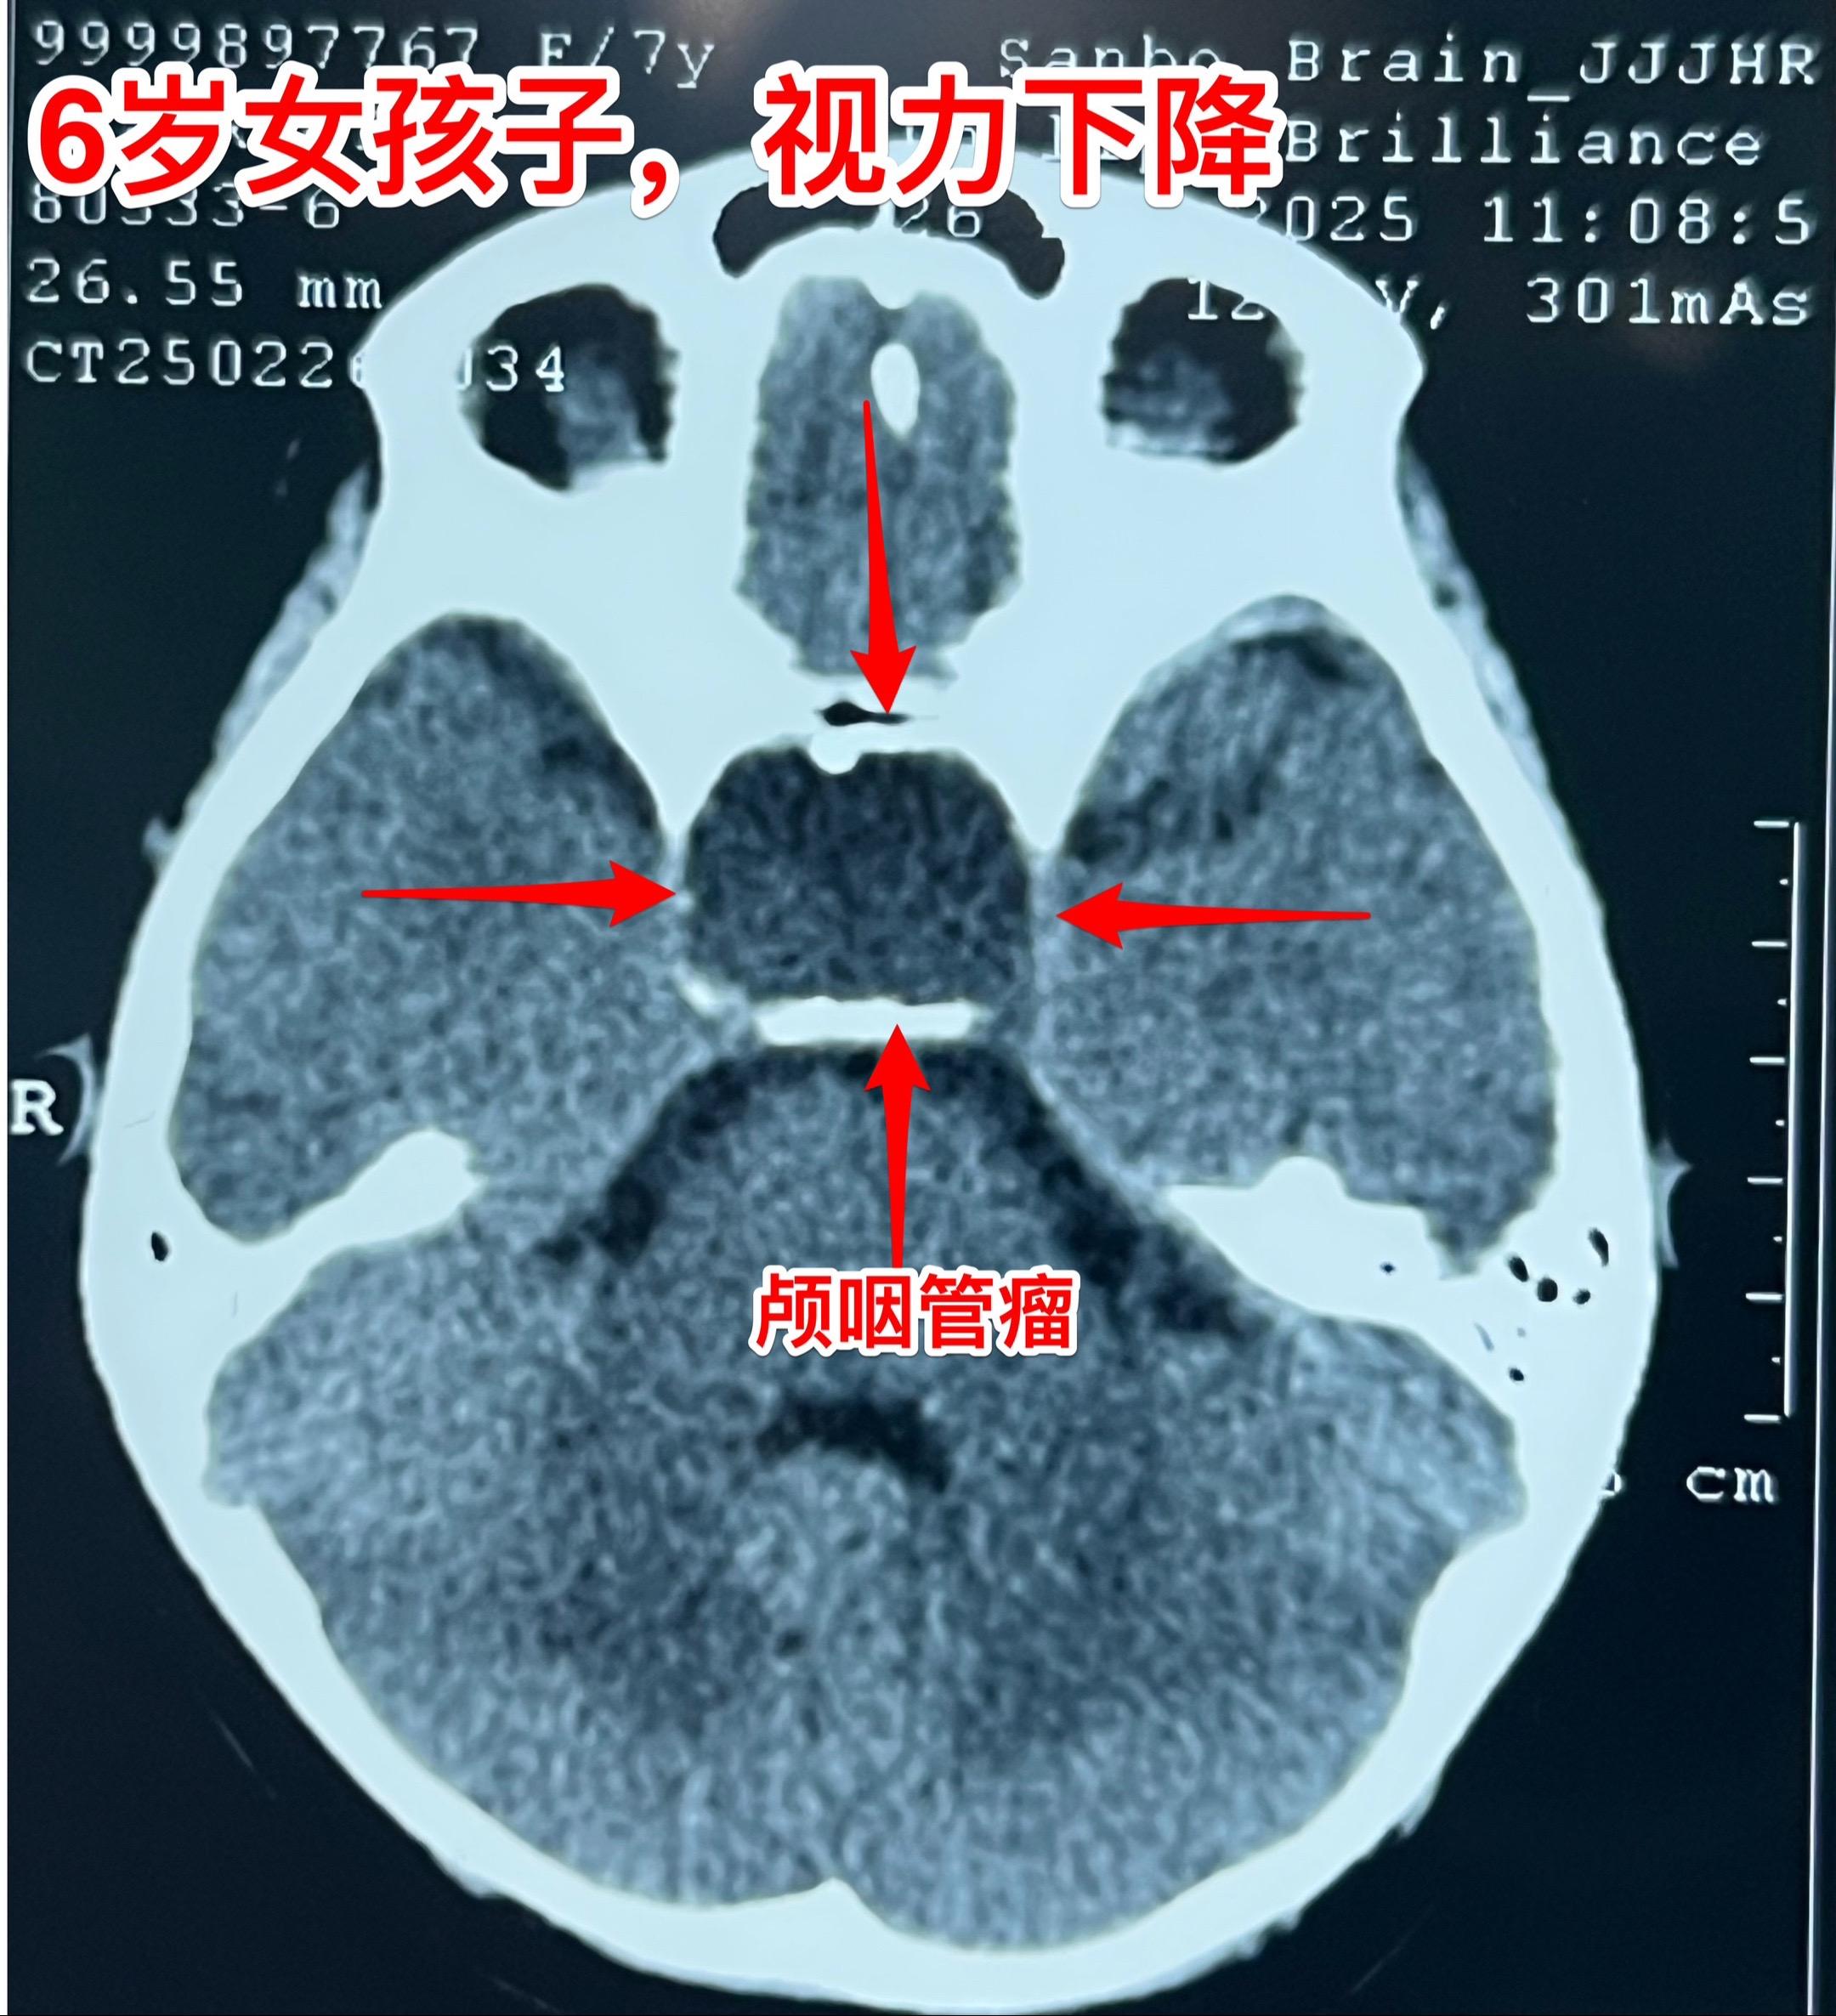

小学生的视力家长一定要关注。小学生因岁数小,对视力下降很可能并不知道表述。所以家长一定要密切观察孩子的视力变化。如果 孩子在很近距离才能看清书上的字,或者看电视距离时喜欢靠近电视机很近才能看清楚,家长就要想到孩子的视力出了问题。我在之前的视频中曾经提到过类似的悲惨事件。 今天说的是六岁郑州小女孩,于2月22日在家写字时居然无法看清作业本上的方格了!家长这才发现孩子的视力很差了,快接近失明了。 2月23日行磁共振检查,发现鞍区肿瘤。3月25日行CT检查,发现肿瘤有钙化,可以确诊